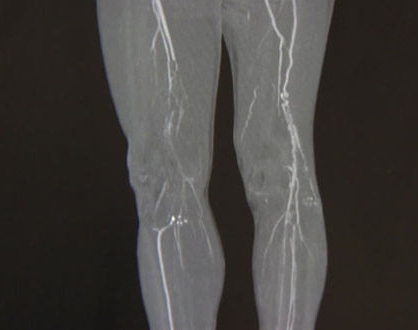

하지의 혈관순환장애 오랫동안 서 있거나 앉아 있으면 다리가 뻐근하고 통증이 있는데, 하지의 정맥 순환에 문제가 있기 때문일 수 있다. 노화되거나 여러 가지 이유로 혈관에 무리가 가 정맥혈을 막는 판막이 역류하면 정맥혈이 정체될 수 있다. 정맥순환장애가 있으면 다리가 쉽게 붓고, 비좁은 느낌이 들고, 쉽게 피로해지고, 경련이 자주 생긴다. 이러한 증상이 심해지면 하지정맥류가 생기기도 한다. 하지정맥류는 동맥질환과 달리 생명에 지장이 있는 증상이 거의 나타나지 않는다. 그래서 "조금 불편하고 보기 싫다"며 오랫동안 방치하는 이들이 많다.

하지정맥류가 치료되지 않아 병이 심해지면 튀어나온 혈관이 두꺼워진다. 피부색 변화, 피부염, 피부궤양, 하지정맥류 등 다양한 합병증이 발생한다. 부기가 만성화되면서 하체비만으로 이어진다. 우리는 비정상적인 종아리 근육통의 다양한 증상과 원인을 조사했다. 자신에게 해당되는 증상이 의심되면 병원을 찾아 진단을 받는 것이 좋다. 처음에는 병을 잡아야 해요! 기억해!